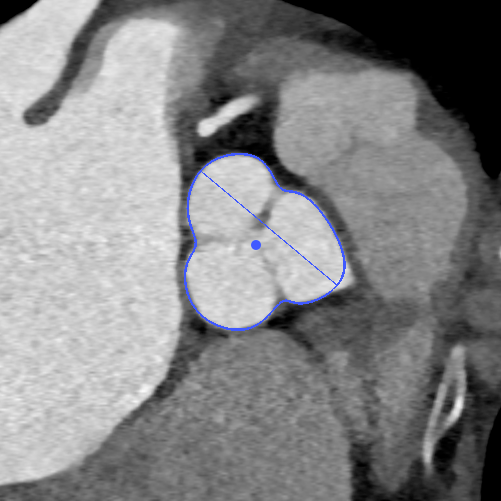

CT测量

主动脉根部CT

瓣环平均直径:

22mm

左室流出道平均直径:

23.3mm

窦宽:32/30/31mm

横位心:48°

左冠开口高度:

13.5mm

右冠开口高度:

10mm